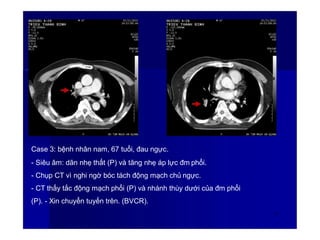

Case 3: bệnh nhân nam, 67 tuổi, đau ngực.

- Siêu âm: dãn nhẹ thất (P) và tăng nhẹ áp lực đm phổi.

- Chụp CT vì nghi ngờ bóc tách động mạch chủ ngực.

- CT thấy tắc động mạch phổi (P) và nhánh thùy dưới của đm phổi

(P). - Xin chuyển tuyến trên. (BVCR).